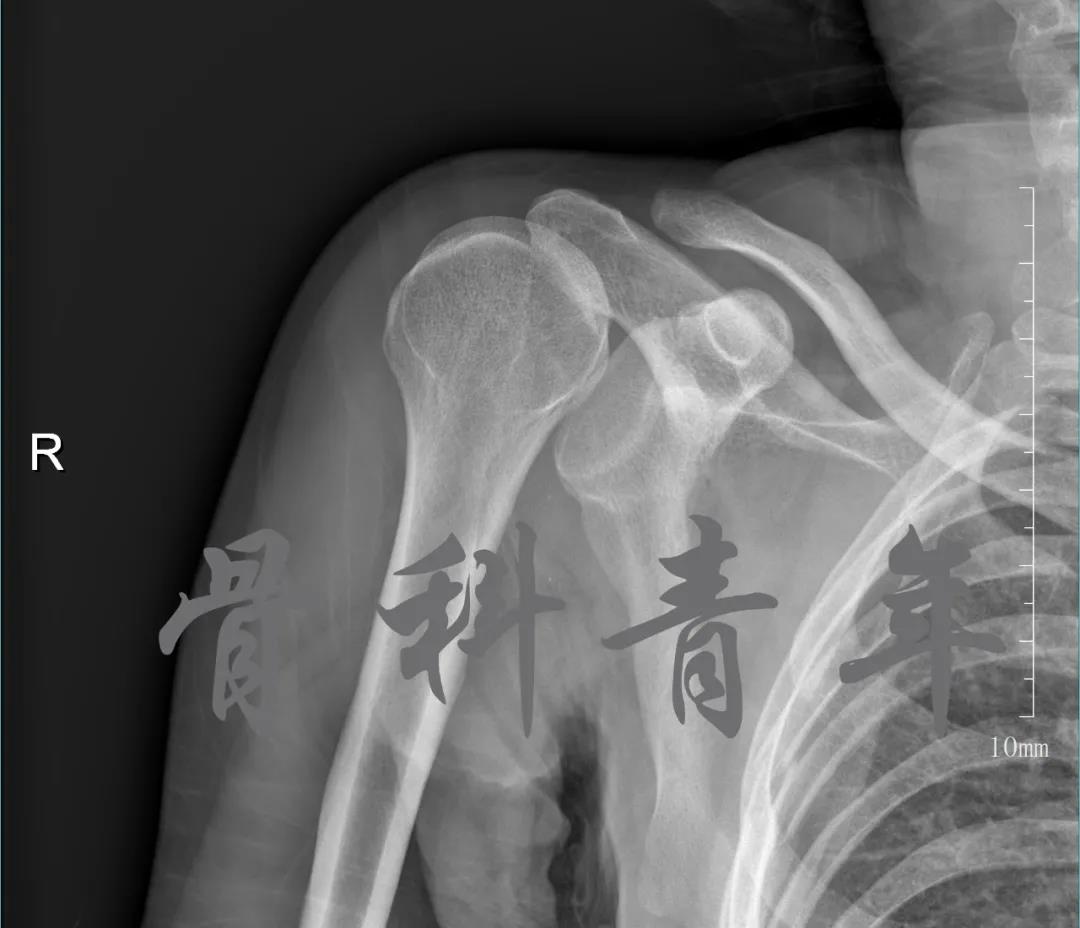

简要病史:骑摩托车跌倒致左肩部肿痛,活动受限,就诊于当地医院,拍片及磁共振检查后诊断为肩袖损伤及肩关节半脱位,予以悬吊固定,因症状缓解不明显就诊于我院。外院拍片情况如下:

应该说是一个典型的“灯泡征”影像,但是并未引起注意。

当地接诊医生应该说还是很负责的,同时拍了健侧片对比:

影像科报告,骨科医生光看报告行吗?